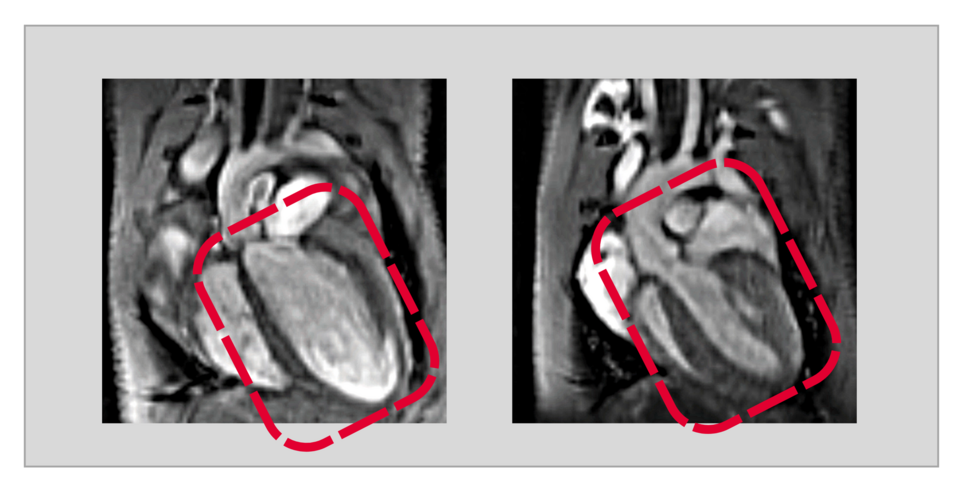

„Durch einen gentechnischen Eingriff konnten wir in den Herzmuskelzellen ausgewachsener Tiere USP5 gezielt ausschalten. Fehlte dann das USP5, entwickelte sich in der Folge eine dilatative Kardiomyopathie“, berichtet Silke Kreher. Co-Autorin Yvonne Eibach fügt hinzu: „Mit Hilfe der Magnetresonanztomographie als Bildgebungsverfahren konnten wir eindrucksvoll nachweisen, dass bei diesen Tieren das gesamte Herz deutlich vergrößert und die Pumpleistung stark eingeschränkt ist.“